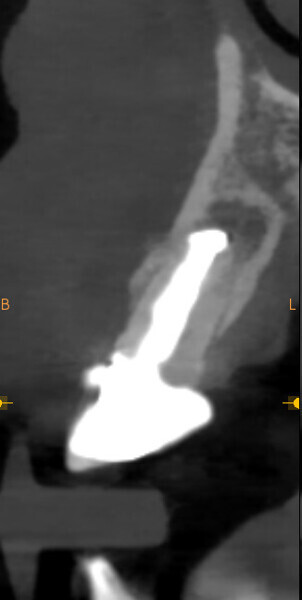

The first step was to obtain a CBCT scan of the maxillary arch, which revealed periapical pathology in teeth #12-22 (Figs. 2 & 3). Furthermore, tooth #21 exhibited significant loss of buccal bone, and a small piece of amalgam was identified in the bone near tooth #21. After a thorough analysis of the radiographic findings, a treatment plan was established to extract teeth #12-22 and perform ridge preservation to reduce bone loss in the extraction sites.

Fig. 3: Initial CBCT scan. Coronal view of tooth #21 showing buccal bone loss.